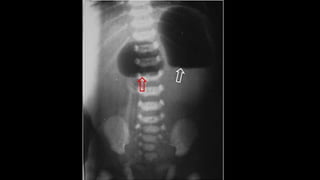

SIGNO DE LA LÍNEA DEL PSOAS

• Utilizado en el diagnóstico diferencial de la patología

intraabdominal y la retroperitoneal.

• El borramiento de la línea del psoas sucede en procesos con

alteración de la radiotransparencia de la grasa

retroperitoneal(infiltración por sangre, edema, líquido o

tumoración).

• La línea del psoas puede no verse en hasta un 40 % de sujetos

normales y puede estar conservada la línea en presencia de

patología retroperitoneal, por lo que su utilidad es muy escasa.

SIGNO DE LALÍNEA DEL PSOAS • Utilizado en el diagnóstico diferencial de la patología intraabdominal y la retroperitoneal. • El borramiento de la línea del psoas sucede en procesos con alteración de la radiotransparencia de la grasa retroperitoneal(infiltración por sangre, edema, líquido o tumoración). • La línea del psoas puede no verse en hasta un 40 % de sujetos normales y puede estar conservada la línea en presencia de patología retroperitoneal, por lo que su utilidad es muy escasa.